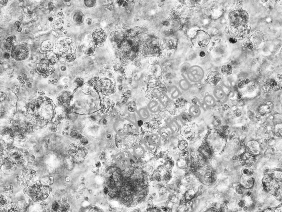

涉及交联剂向内扩散以进行原位凝胶化的生物打印策略

交联剂扩散:将未交联的海藻酸钠墨水挤入含钙离子的支撑浴中,钙离子扩散至墨水中形成离子交联,稳定打印结构。

pH诱导凝胶化:胶原墨水在碱性缓冲液的扩散下,pH升高触发自组装成纤维网络。